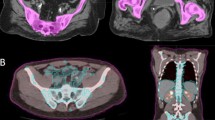

All patients underwent planning computed tomography in supine position with intravenous contrast medium and 5 mm slices. The clinical target volume (CTV) was based on common target volume delineation guidelines (RTOG) and consisted of the uterus, cervix, parametria, upper half of the vagina if involved and regional lymph nodes. The paraaortic nodes were included if radiographically involved and a planning target volume (PTV) was defined using an isotropic margin around the CTV of 10 mm adopted to anatomical structures. Six patients were treated in IMRT technique with helical tomotherapy, 23 patients had a VMAT and two patients had a step-and-shoot IMRT plan.

Definition of bone marrow-relevant substructures

The pelvic bone included the os sacrum, os ilium, os ischii and os pubis. The femoral head included the upper femur, the bone cortex was also included. The lumbar spine was not included. The dosimetric parameters were defined as the volumes of a definite radiation dose, such as Vx means the total volume of the bone that received the radiation dose of X Gy. In addition, the analyzed parameters included the V5, V10, V20, V30, V40, V50, and the minimal, maximal and mean doses. Patients with paraaortic RT were excluded from dosimetric analyses of BM subvolumes.

Although most of this work has defined the bony structures as BM equivalent, some authors proceed methodologically differently. These take positron emission tomography (PET) as the basis of the BM definition to define active BM [13, 17]. The FDG uptake in PET/CT scans can define active BM regions and correlates with the number of hematopoietic marrow cells [7, 18]. The uptake within the radiation field decreases after treatment and is variable across irradiated bone sites, which indicates myelosuppression [18]. In conjunction with the use of modern radiation techniques such as IMRT and VMAT, this methodology offers greater accuracy when trying to spare relevant BM subvolumes in order to reduce toxicity.

The group of Mell and colleagues initiated a remarkable prospective multicenter phase II trial, which examined for the first time the dosimetric impact and relevance of PET-based BMS-IG-IMRT [13]. The BM constraints used were V10Gy and V20Gy < 90% and < 75%, respectively. The results showed that V10Gy/V20Gy/V30Gy/V40Gy were considerably lower with IG-IMRT and led to significantly less grade-3 neutropenia. The same group was able to set up the international phase-II/-III trial (INTERTECC) that accrued 101 patients, which is also the most relevant study in this field today[19]. The question of the study was whether PET-based bone marrow sparing IG-IMRT reduces toxicity compared to standard IG-IMRT. The results showed a significant lower incidence of acute grade ≥ 3 neutropenia in the PET-BMS-IMRT group as compared to IMRT (19% versus 54%), but no difference in post-treatment ALC by treatment group. Furthermore, according to the authors there was no evidence that PET-BMS-IMRT affected chemotherapy delivery or long-term outcomes. However, only 29 out of 101 patients were finally enrolled in the phase-III part and a possible bias cannot be excluded.